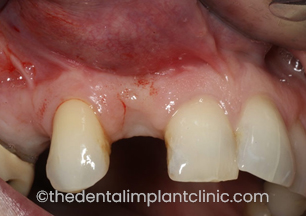

Implant placement to replace single missing teeth. In this instance, the teeth that were missing are the patients upper right first premolar (UR4) and lateral incisor (UR2) teeth.

Missing upper right lateral incisor (UR2) and first premolar (UR4) teeth